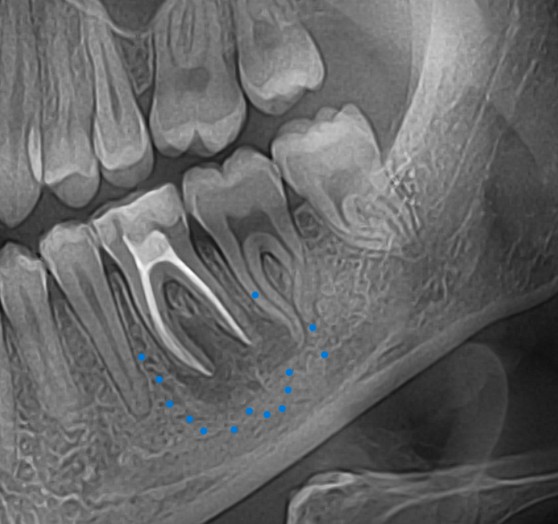

Perforáció (fenti kép)

Tű-törése (fent)

Feltáratlan gyökércsatorna (fent)

Anatómiai okok a sikertelenség esetén:

Elmeszesedett csatorna

Kialakult endo-parodontális lézió